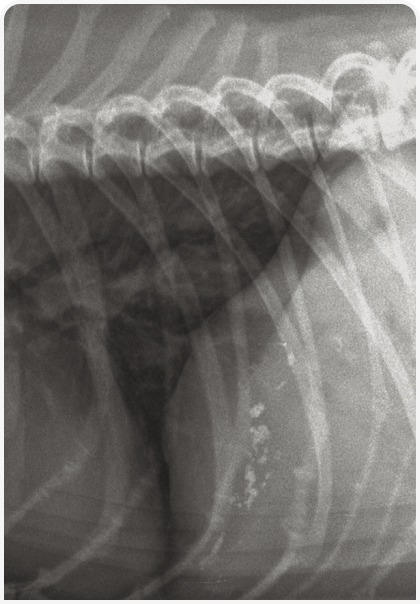

В норме поджелудочную железу на рентгеновском снимке идентифицировать невозможно, поскольку она слишком мала. Однако у некоторых кошек с избыточной массой тела и большим количеством внутрибрюшного жира левая доля поджелудочной железы визуализируется рядом со средней частью селезенки, прилегая к краниальному полюсу правой почки, и ее не следует ошибочно считать патологическим образованием. Рентгенография может быть полезна при подозрении на заболевание поджелудочной железы, поскольку панкреатит может сопровождаться косвенными изменениями, такими как снижение четкости серозной оболочки в краниальных отделах брюшной полости, увеличение пилородуоденального угла, расширение просвета двенадцатиперстной кишки газами вследствие индукции вторичной функциональной кишечной непроходимости. Кроме того, некоторые опухоли поджелудочной железы могут подвергаться минерализации, и при выявлении в краниальном отделе брюшной полости объемного образования с очагами минерализации можно заподозрить его происхождение из поджелудочной железы.